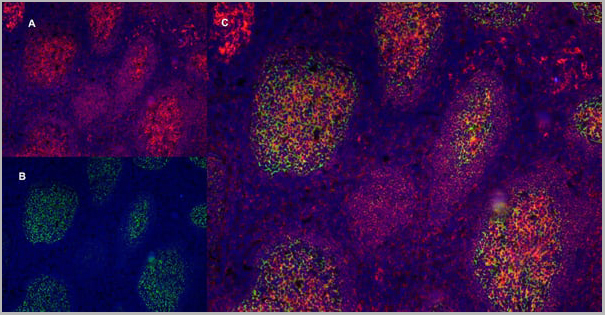

Application Data

(Immunofluorescence staining of a human tonsil cryostetion with Mouse anti Human CD40 antibody, clone LOB7/6 , red in A and Mouse anti Human CD21 antibody, clone LB21 , green in B. The merged image is C with nuclei counterstained blue using DAPI. Low power)